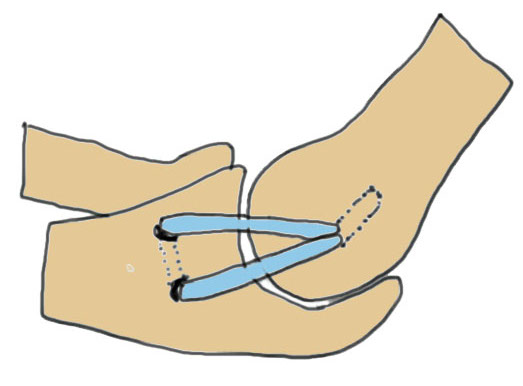

Palmaris longus - present 85% / press thumb and finger together